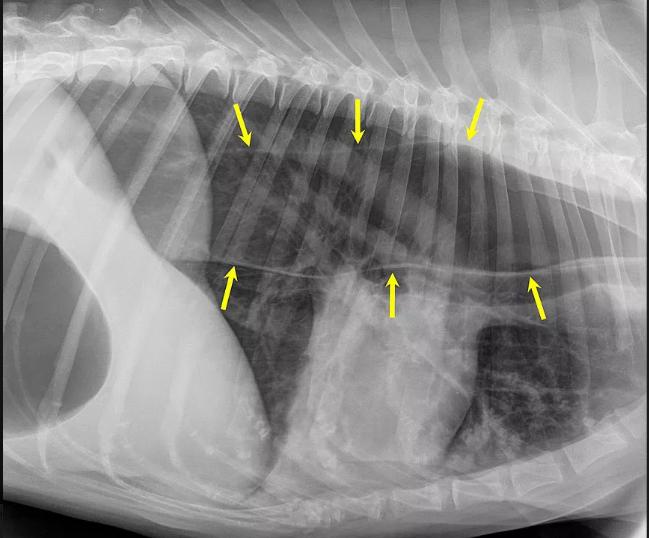

巨大食管症也叫做食管扩张,在人类与狗狗身上都会出现,而简单来说,这种疾病会让狗狗的食管变大变宽。食管是由光滑薄弱的肌肉与粘膜组成的一个管道,如果狗狗的神经功能运作正常,食物会通过食管蠕动,缓缓从口腔滑入胃中。而患有巨大食管症的狗狗食管无法正常蠕动,因此食物可能会卡在食管中,无法进入胃里面或者被吐出来。